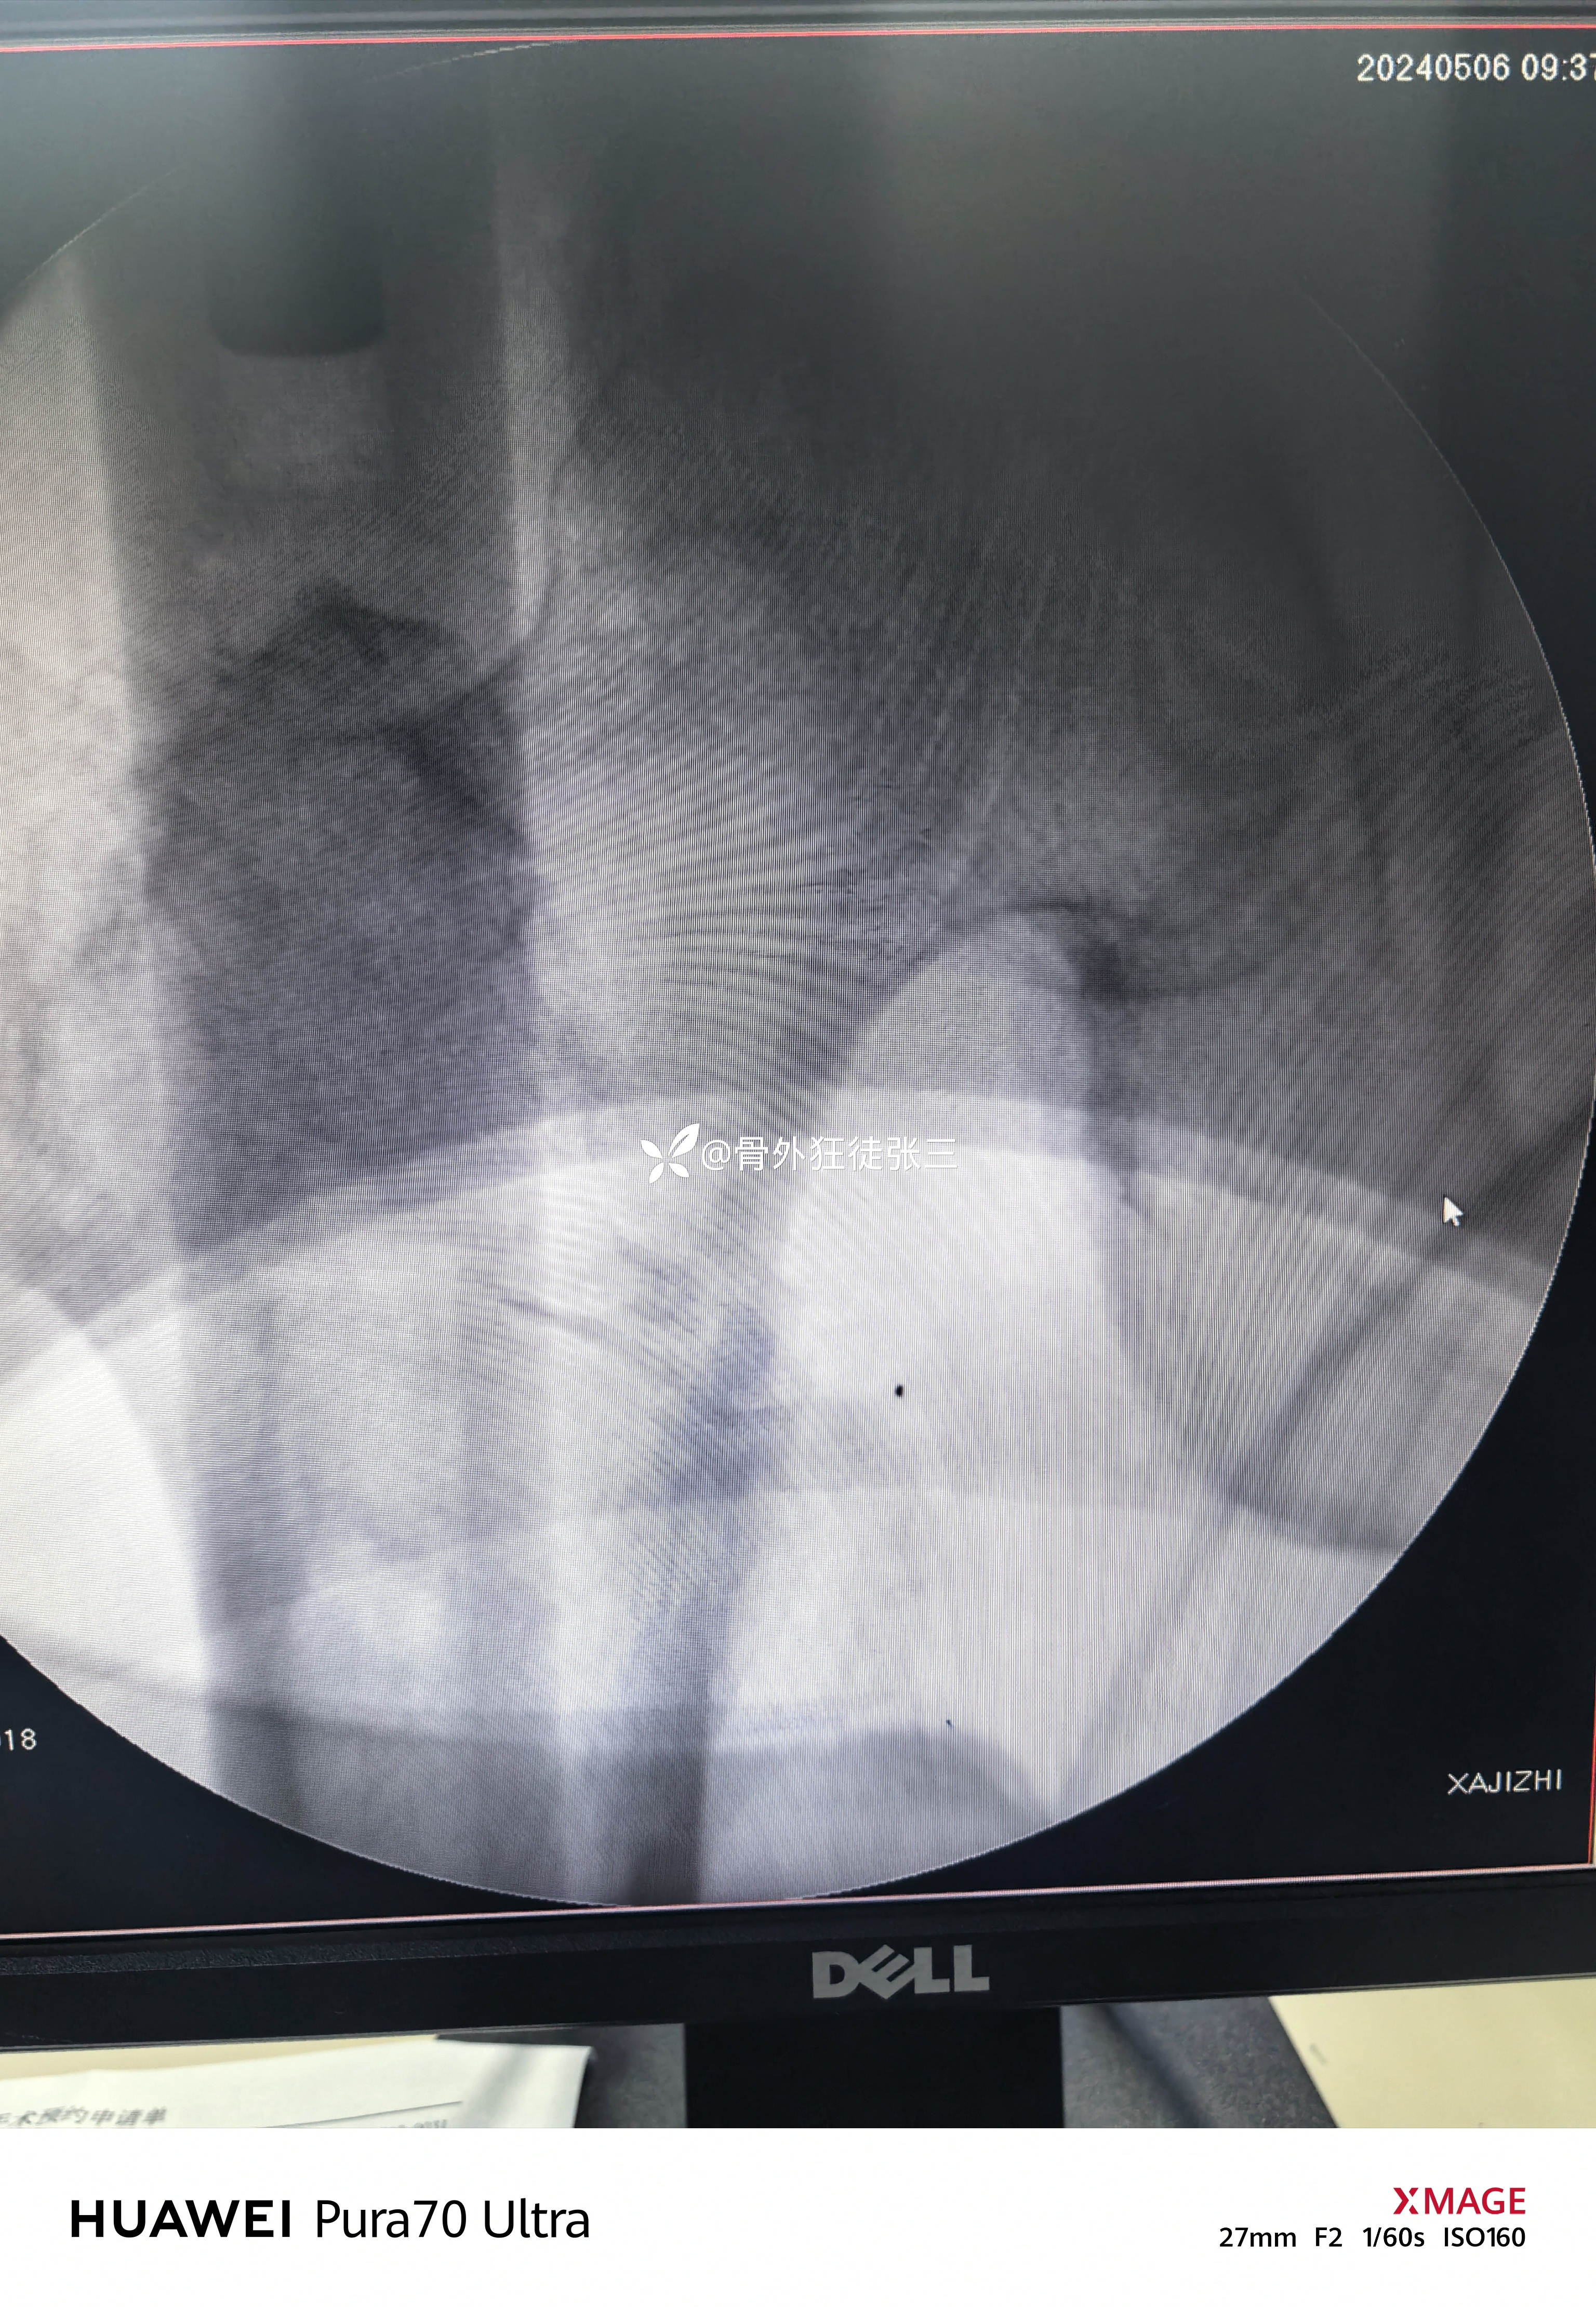

牵开器——透视正侧位——切口——确定进针点——铰刀开口——开口钻开口——金手指——导针置入——直接使用170 mmX12 mm主钉插入——调整前倾主钉深度和前倾——透视正位中下1/3,侧位基本居中——远端锁钉——近端锁尾端尾帽,——再次透视正、侧、蛙位——冲洗、缝合1-1-3 ——09:37-10:16 ——40分钟手术结束,透视16次,每次约一分钟,手术操作20分钟。

没有再调整主钉和螺旋刀片

术后复查

螺旋刀片还能再长5mm